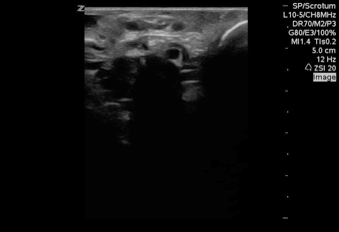

Big p0ints if you can nail this diagnosis. Almost never see it in the developed world unless you are like this patient who recently travelled to Uganda.

He had scrotal pain for weeks, misdiagnosed as sexually transmitted infectious despite negative testing.

Answer: filariasis.

See the multiple cystic looking structures next to the testicle? Those are not blood vessels. Time to call up the CDC for some experimental treatment.